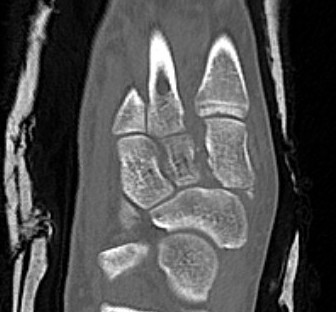

CT

Fleck sign

Fleck sign with inter-cuneiform widening

Dorsal subluxation of the metatarsal